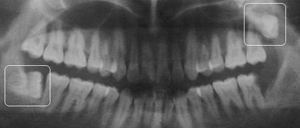

2、智齿位置:智齿所处的位置、需拔数量、生长怪异程度、病变程度的不同,其拔牙难易程度不同。有些患者智齿结构为复杂,在拔智齿前需进行拍X光片以了解智齿的底部结构。一般说来,上颌智齿结构简单,较容易拔除,因此上颌拔智齿价格较下颌拔智齿价格便宜。

1、侵犯邻牙:通常患者不自知,而由牙医以X光诊断得知,通常智齿萌发的空间不足,而会倒在第二大臼齿上,因而造成第二大臼齿清洁不易,甚至是牙齿部分吸收的现象,造成患者不 或牙疼。